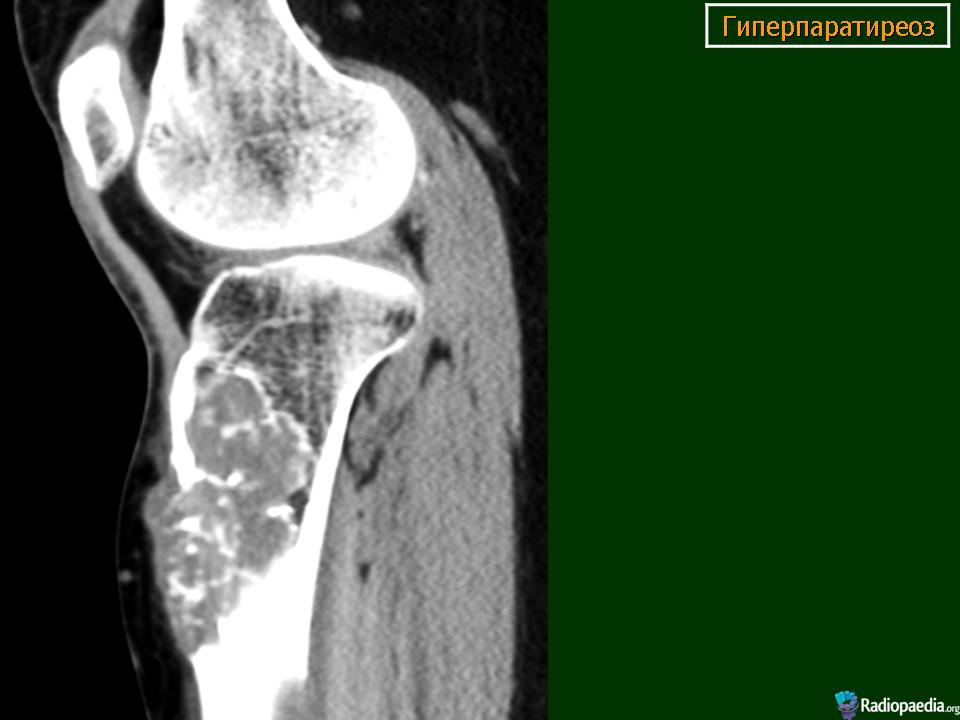

Пораженные длинные трубчатые кости несколько вздуты. Это цилиндрическое утолщение захватывает весь диафиз, метафизы также представляются несколько вздутыми. Кортикальный слой неравномерно истончается, может быть бугристым. Эпифизы, как правило, мало изменены. Характерна деформация метадиафиза бедренной кости по типу «пастушьей палки». Область большого вертела поднимается, анатомическая шейка бедренной кости располагается горизонтально, диафиз О-образно искривляется. Характерна также варусная деформация проксимального отдела плечевой кости. Деформации обычно не симметричны. Достаточно быстро развивается деформация костей таза в виде «карточного сердца». Реакция надкостницы отсутствует и лишь при патологических переломах, может выявляться незначительная периостальная реакция.

На рентгенограммах определяется перестройка костной структуры в виде очагового или диффузного крупнозернистого остеопороза. Характерна кистозная перестройка костной структуры. Кисты располагаются, как в зоне костномозгового канала, так и интракортикально. Форма их - овальная, вытянутая по длиннику кости. Кисты могут быть одиночными и множественными. Часто кисты сливаются одна с другой и в зоне костномозгового канала они имеют нечеткие контуры.